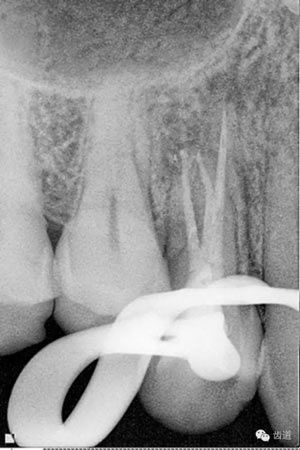

處理:放置橡皮障,去除暫封,超聲結(jié)合2%CHX清除遠(yuǎn)頰根管內(nèi)氫氧化鈣糊劑,主牙膠試合后95%酒精沖洗干燥根管,結(jié)合AH Plus糊劑連續(xù)波熱牙膠垂直加壓充填根管,樹脂分層粘接修復(fù)牙體。建議定時(shí)復(fù)診進(jìn)行嵌體修復(fù),患者未執(zhí)行。